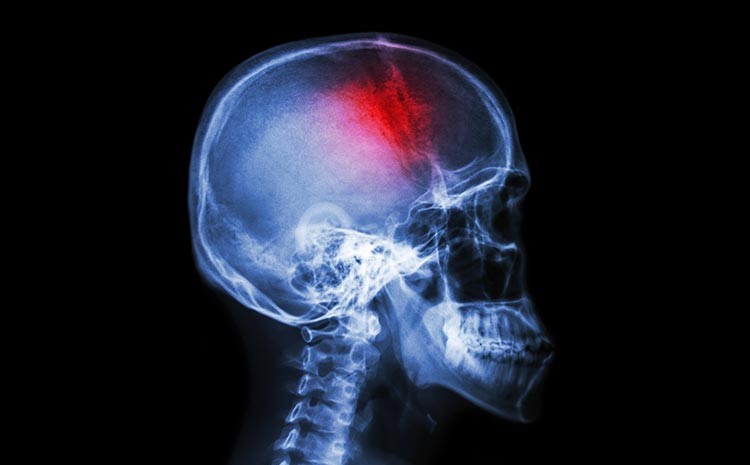

Há momentos na vida em que o tempo parece desacelerar. Outros, em que ele simplesmente desaparece. O início de um AVC — o acidente vascular cerebral — pertence a essa segunda categoria. Não há aviso claro, não há preparação emocional. Apenas um corpo que, de repente, deixa de responder como antes.

O cérebro depende de um fluxo constante de sangue para funcionar. Quando esse fluxo é interrompido, como no AVC isquêmico, ou quando há sangramento, como no hemorrágico, inicia-se uma corrida silenciosa contra o tempo.

Não se trata de um dano imediato e uniforme. Existe uma área mais comprometida e outra ao redor que ainda resiste. Essa região intermediária, muitas vezes invisível para quem observa de fora, é onde existe potencial de recuperação — e onde o tempo exerce maior influência.

O paciente não percebe exatamente esse processo acontecendo. Mas, do ponto de vista clínico, cada minuto sem intervenção pode significar perda progressiva de funções importantes, como movimento, fala e autonomia.

É por isso que, nas primeiras horas, o tempo deixa de ser abstrato. Ele passa a ser um fator concreto na preservação daquilo que ainda pode ser salvo.